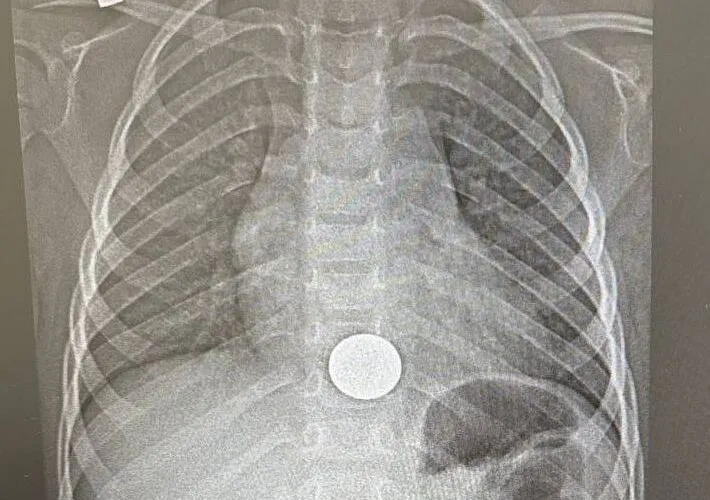

Трёхлетнего ребёнка, проглотившего монету, спасли врачи Нижнекамской детской районной больницы с перинатальным центром, сообщили в пресс-службе медучреждения.

Малыш поступил с жалобами на боли за грудиной. Как выяснилось, он взял монету у старшего брата поиграть и случайно проглотил её. Мама незамедлительно отвезла сына в больницу, где рентген подтвердил: монета застряла в пищеводе.

Хирург с помощью эндоскопа удалил монету — процедура заняла около минуты. После этого ребёнка перевели в хирургическое отделение, а на следующий день, убедившись, что его состояние в норме, выписали домой.